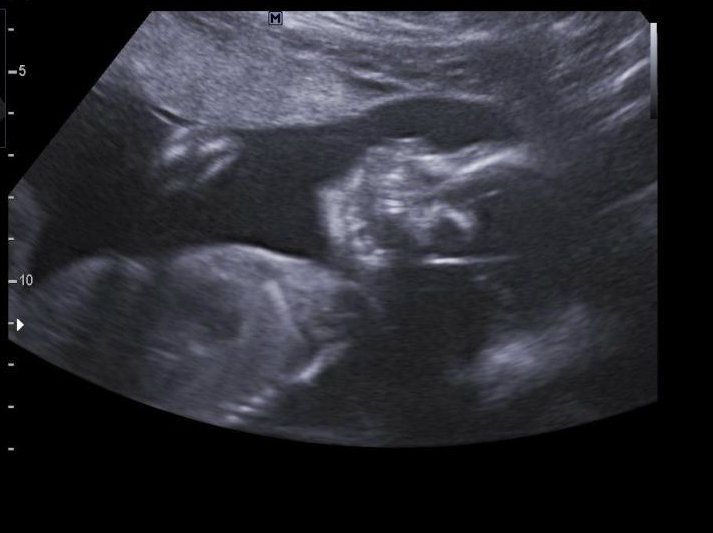

Had our follow up anatomy scan ultrasound today so they could get the other heart measurements that were missing from last time. He was kicking the whole time, but everything looked perfect and it was so easy to see! He is head down of course, which makes me kind of wonder what I'm going to "miss out on" but things can change too! I'm still going ahead with my csection regardless. We saw his little hands and feet and he was facing perfectly so we got a profile and the front of his face, soooo cute! We left the girls at home with grandma so Justin and I were able to sit and stare at the screen without any interruptions and it was nice! I always miss my girls, but a little breathing time is good for the soul too!

Size of baby - Baby measured 22 weeks exactly today (he lost a few days, which I'm trying not to worry about from past experience) and he weighs exactly 1lb! I'm not sure how long he is, I don't think they can really tell from the U/S but he should be approximately 11.5 or so inches. He's a perfect little miniature baby, just needs to fatten up in the next months!